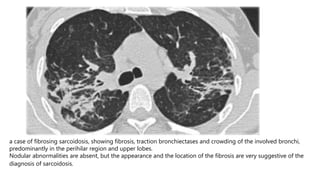

a case of fibrosing sarcoidosis, showing fibrosis, traction bronchiectases and crowding of the involved bronchi,

predominantly in the perihilar region and upper lobes.

Nodular abnormalities are absent, but the appearance and the location of the fibrosis are very suggestive of the

diagnosis of sarcoidosis.